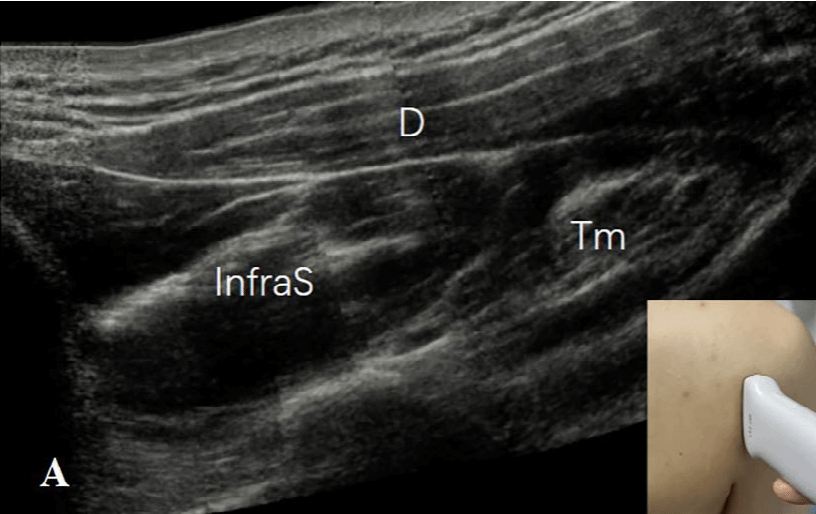

探头的位置根据三个解剖标志来确定:四边孔、肩胛下肌的前方和腋动脉的后方。1)四边孔:由上方的小圆肌、下方的大圆肌、内侧的肱三头肌长头和肱外侧的骨外科颈构成。在评估这个区域时,患者取坐位,肩部处于中立位置。探头沿纵向放置在肩胛骨的外缘和肩胛骨下角下方,以显示冈下肌和小圆肌的短轴切面(图2A)。探头沿着矢状面向外侧移动,直到出现肱三头肌长头腱(图2B)。在这一切面上,小圆肌位于肱三头肌长头的头侧和浅方,大圆肌位于足侧和深方。探头继续向外侧移动,直到出现肱骨干(图2C)。在此切面上,腋神经(AN)和旋肱后动脉位于由头侧的小圆肌(Tm)、足侧的肱三头肌长头(Tr)、浅方的三角肌(D)和深方的肱骨干围成的空间内。通过调整探头,可以更清楚地显示神经血管束(图2D)。

图2A:探头沿着矢状面放置在肩胛骨的外缘和肩胛骨下角下方,以显示冈下肌(InfraS)和小圆肌(Tm)的短轴。三角肌(D)位于冈下肌(InfraS)和小圆肌(Tm)的表面。